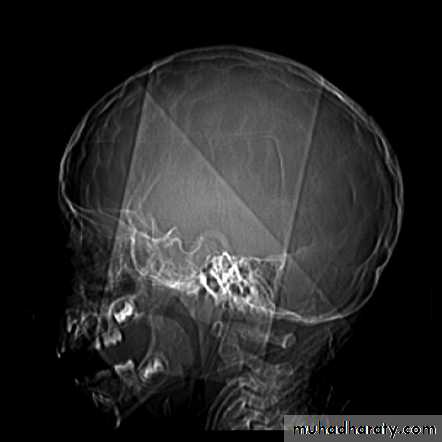

Skull X-ray findings in increased intracranial pressure

• Sutural separation in children.

• ‘Copper-beating’ marking of the cranial vault.

• Thinning of dorsum sellae.

• Erosion of the posterior clinoid process.

Copper-beating’ marking

Neurosurgery